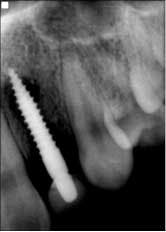

Fig. 3: Implant temporization No. 8 and No. 10 — 3.7 mm x 13 mm implant placed on No. 8.Patient returned one month later after returning from a cruise, complaining that her “implants felt loose.” She was very honest and admitted to not taking the antibiotics and not following any dietary restrictions while on vacation, because “they felt so strong.” Periapicals taken that day showed a catastrophic failure, with large areas of bone loss surrounding both implants (Fig. 4).